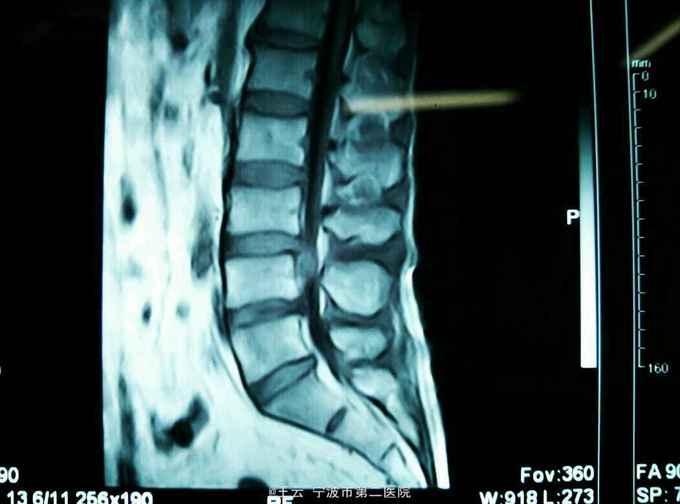

腰3/4椎间盘脱出向下高度游离

患者,女,41岁,因“左下肢放射痛麻木三个月”入院。三个月前有过度劳累史。

查体:左小腿前内侧感觉减退,左侧踝背伸肌力4级,左下肢直腿抬高40度阳性,4字征阴性。

诊断:L3/4椎间盘脱出 治疗:经椎间孔入路椎间孔镜下髓核摘除,射频消融